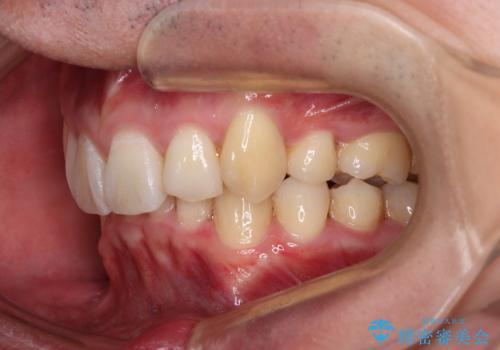

ディープバイトや奥歯の咬み合わせなど、インビザライン矯正では限界がありワイヤー装置での治療に及ばない仕上がりとなりました。

ただし、患者様としては八重歯や、それに伴う唇の閉じにくさが改善されたとのことで、納得いく状態での治療終了となりました。